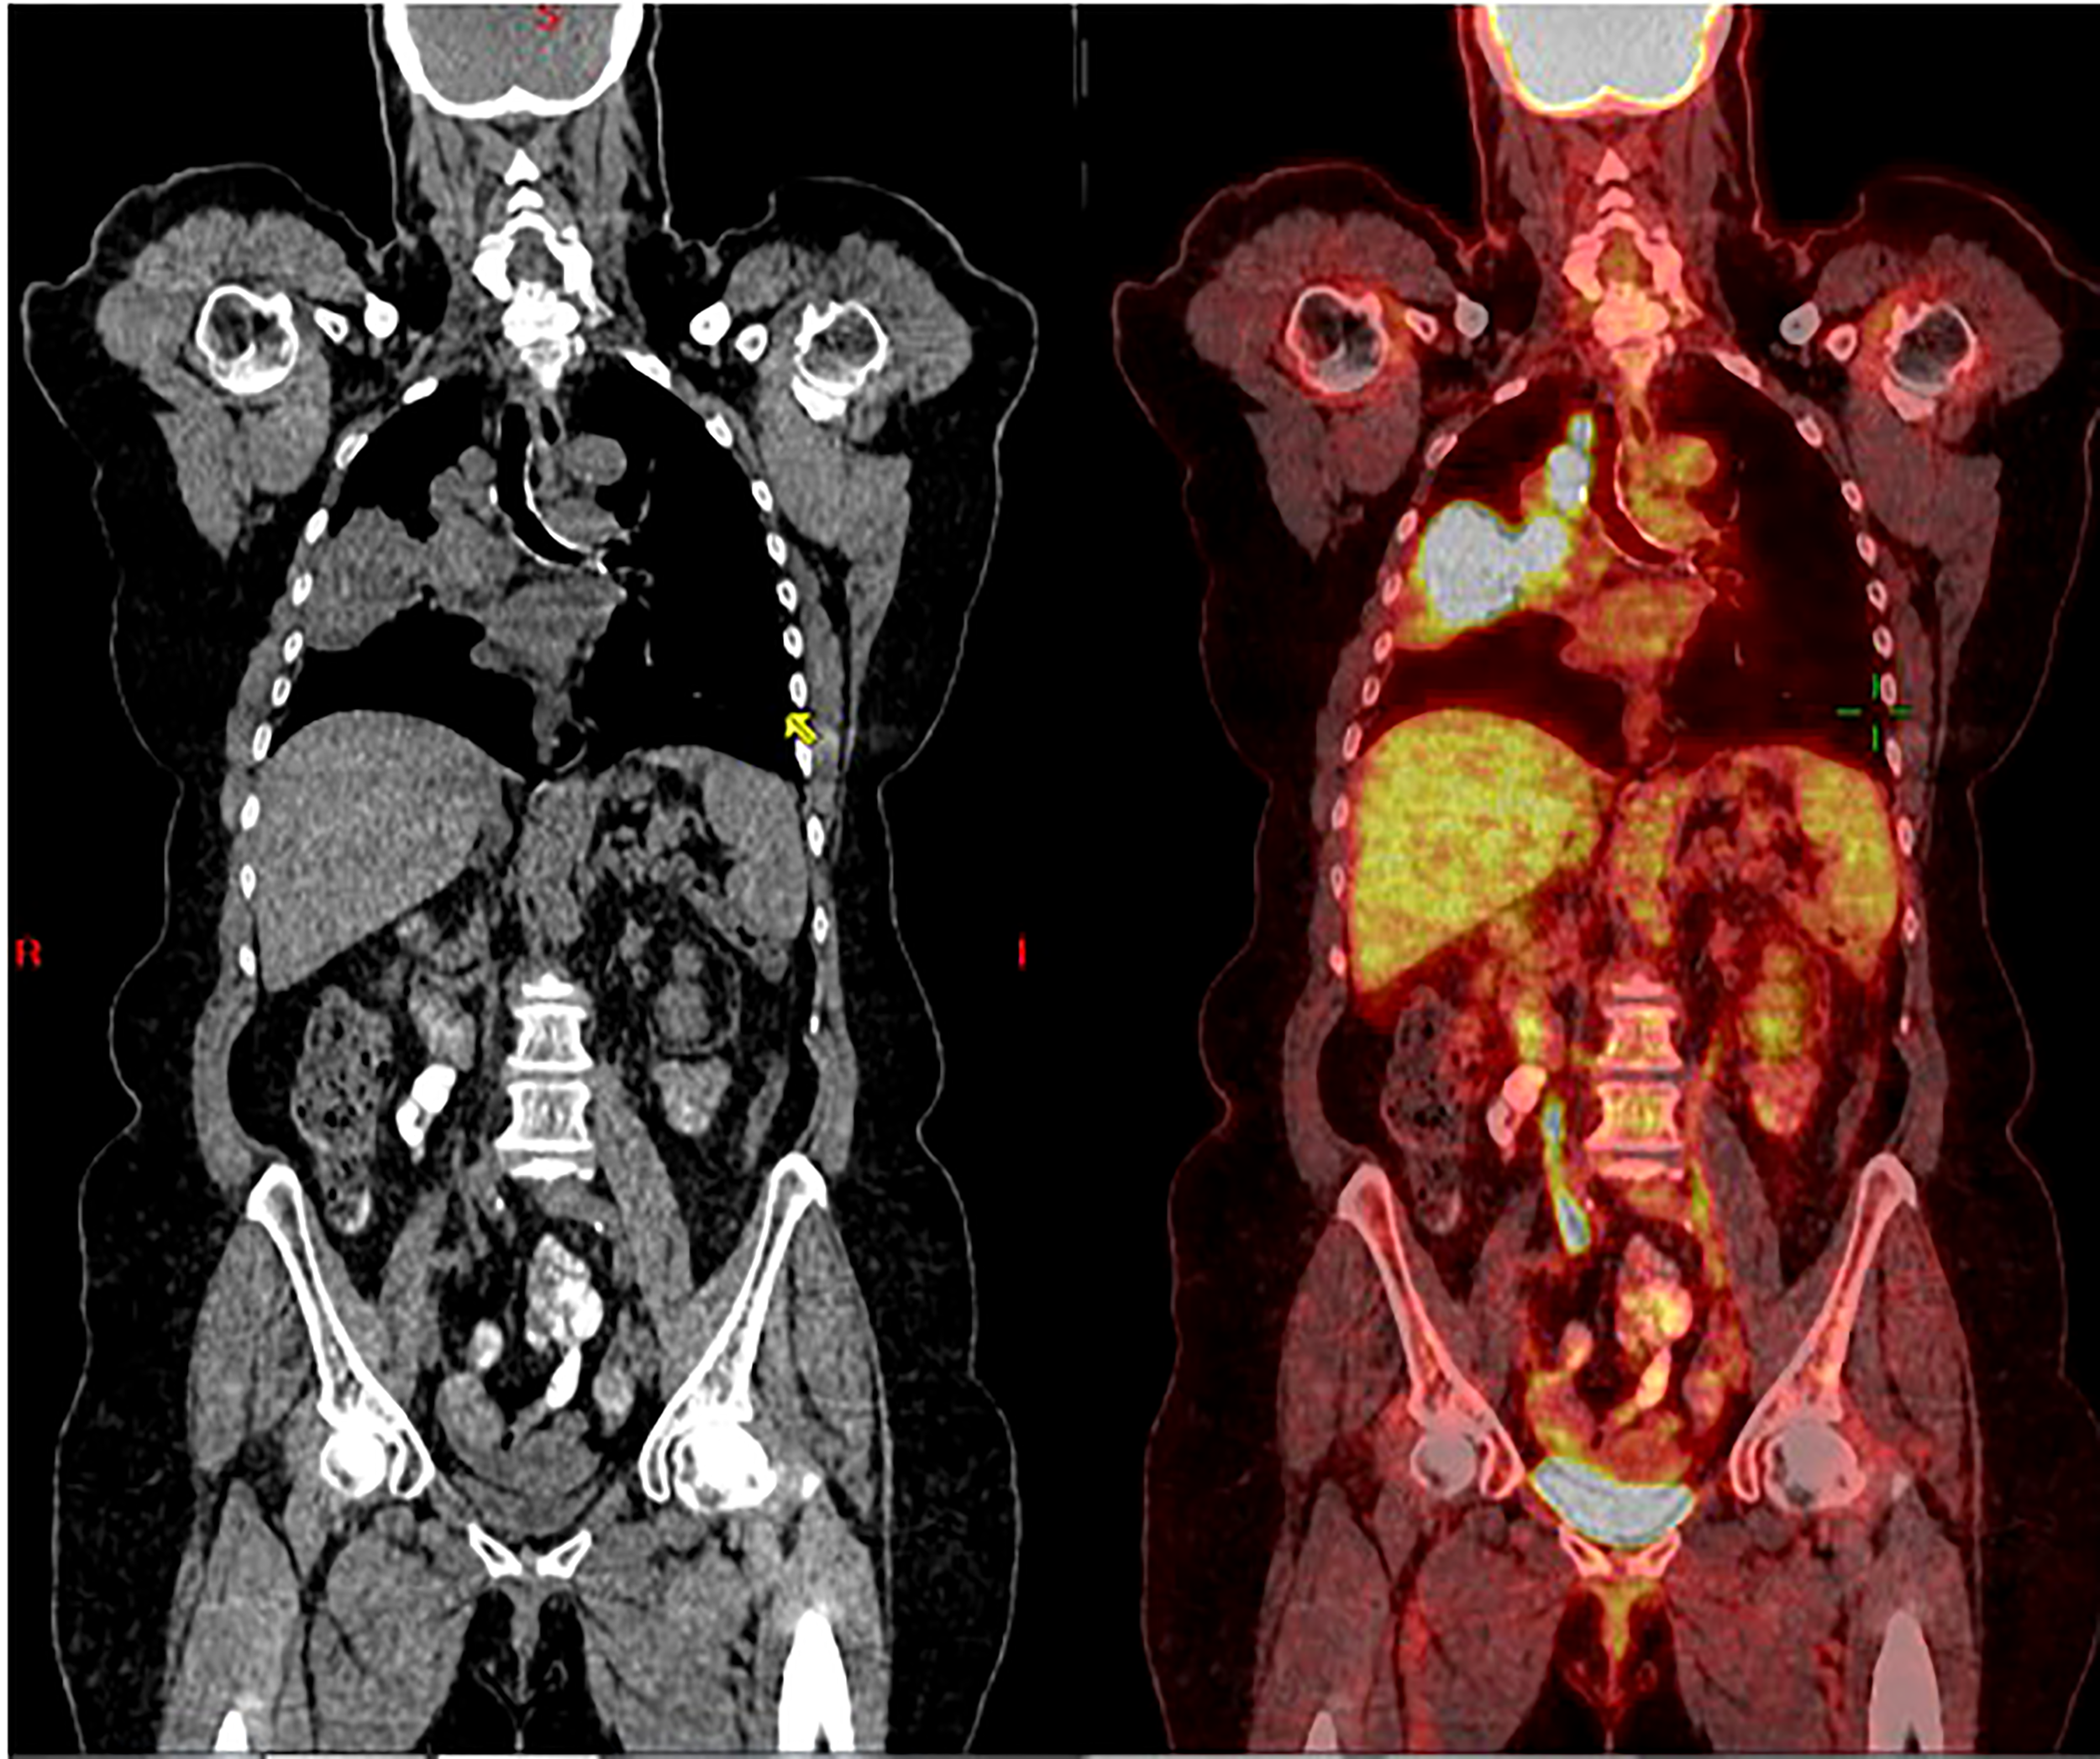

Figure 1

Coronal CT scan (left), and superimposed PET scan (right), from March 2016, show a large right lung mass (>5 cm) with increased uptake of FDG-18. There is also ipsilateral hilar and paratracheal lymphadenopathy with positive PET uptake, contributing to classification as unresectable, stage 3B NSCLC.